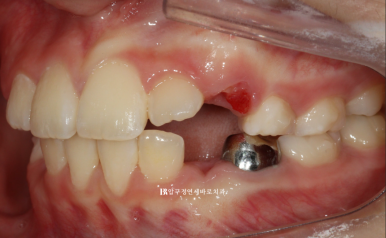

24.3.26

재제작 후 약 3개월 후 모습입니다.

문제가 되었던 치아가 거의 다 배열되었습니다.

이때부터는 치료 없이 유지만 했습니다.

2024.6.4

미리 충분하게 만들어놓은 공간으로 송곳니 등 후속 영구치들이 맹출하고 있습니다.

영구치가 적절한 수준까지 올라오면 고정식 유지장치까지 해줄 계획입니다.

이 친구는 아마 영구치열에 2차 교정이 따로 필요 없을 것 같습니다.